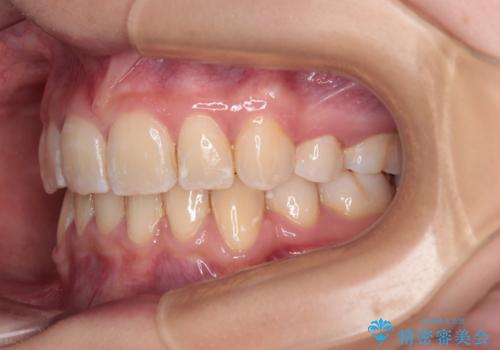

【モニター】出っ歯と八重歯 抜歯矯正でスッキリとした口元に

- 前方に飛び出した前歯と、下顎の八重歯を気にして来院された患者様です。

口元の突出感を改善するため、上下左右の第一小臼歯4本を抜歯し、ワイヤー装置にて矯正治療を行うこととしました。

抜歯矯正により、口元の印象だけでなく、横顔の印象も大きく改善されました。